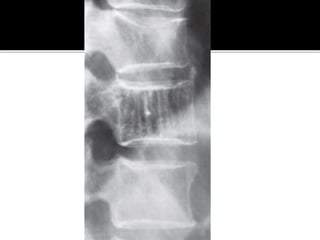

 Common benign bone lesion. 10% population

has asymptomatic lesions in vertebral bodies.

 Skull, long bones uncommon.

 Usually incidental findings.

 Rarely symptomatic unless there is vertebral

collapse or nerve root or cord compression.

 Radiographic appearance – Characteristic

thickened vertically oriented trabeculae –

“Jailhouse” appearance

Cross section – “Polka-dot” pattern

 MRI – bright onT1 andT2 weighted images.

 Asymptomatic – no treatment required

 Vertebral collapse with neurological deficit –

decompression with spinal stabilization.

Long bones – extended curretage

Pre-op embolization to prevent blood loss.

Low dose radiation – risk of malignant

transformation